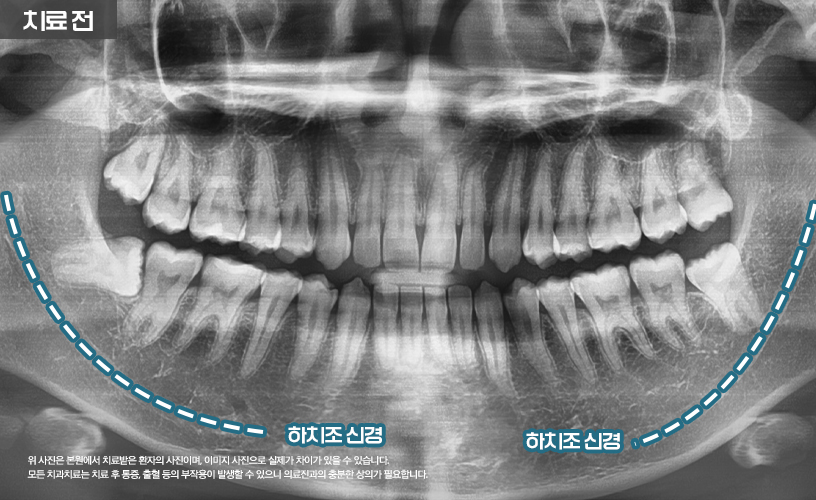

상기 환자분은 하악 매복 사랑니로 인해

본 원에서 발치한 사례입니다.

환자분의 경우 하악에 매복된 상태로 있는

사랑니를 확인할 수 있습니다.

특히 #48번 사랑니의 경우

파노라마에 하치조 신경과 겹쳐 보여

CT 촬영을 통해 자세한 검진이 필요합니다.